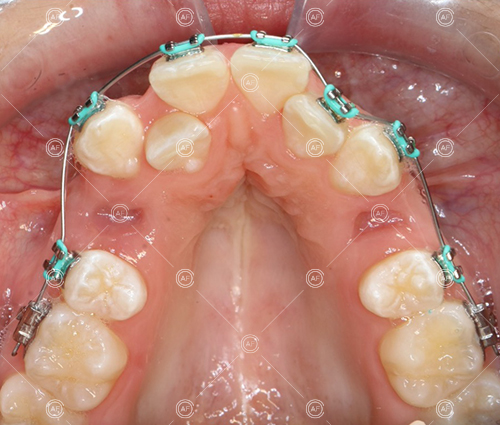

After careful treatment planning, the following treatment plan was formulated:

- Oral hygiene to an exemplary standard

- Extraction of upper right 5, upper left 4, lower left 5, lower right 5

- Fixed appliances in the upper and lower arches

The aim of the treatment was to relieve upper and lower arch crowding, correct lower centre line shift, treat class 1 incisors and buccal segments.

Treatment progressed by starting with thin, flexible nickel titanium archwires of a round diameter, transitioning to a rectangular nickel titanium archwire before eventually working up to a working archwire (1925 stainless steel).